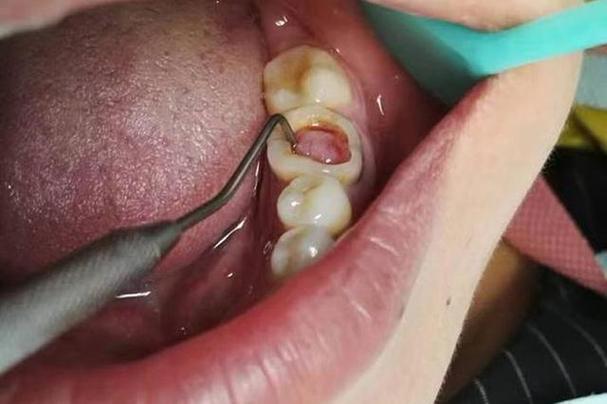

- 中深龋洞的垫底。

- 需要良好边缘封闭和防龋效果的垫底。

- 作为树脂充填的基底(尤其是树脂改性型),提供粘接和氟释放。

- 垫底后可直接在其上充填复合树脂或做嵌体/高嵌体基底。

- 注意: 垫底厚度需足够(通常建议1-2mm),以保证其强度和隔绝效果,树脂改性型因其强度和粘接优势,应用更广泛。